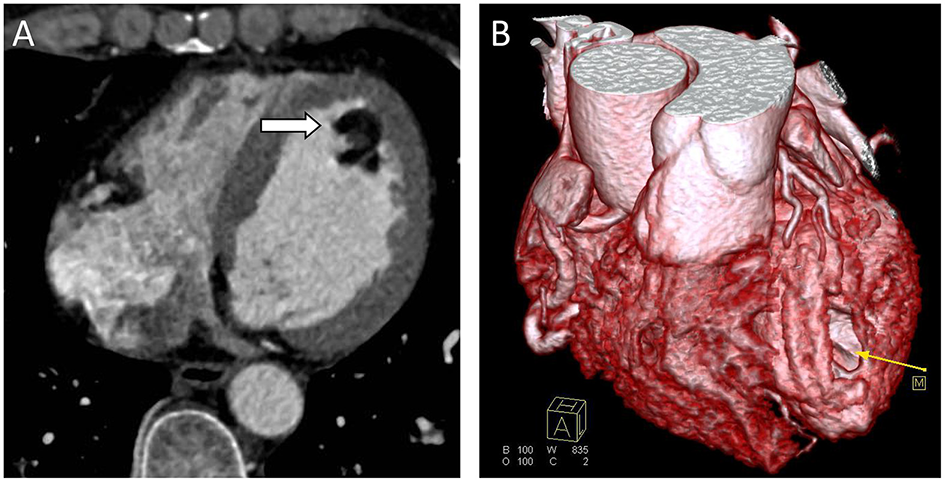

Chest radiograph showed a moderately enlarged cardiac silhouette with increased cardiothoracic ratio and no signs of pulmonary congestion. Transthoracic echocardiogram (TTE) examination showed the following characteristics: aorta 34 mm, left atrium 35 mm, LV cavity 51 mm (end-diastolic diameter), and a hyperechoic mass 30 × 27 mm located on the left side of the heart (middle-apical region), occupying almost 2/3 of the LV with blood supply from the left anterior descending (LAD) coronary artery (Figure 1). The vast mass caused a marked dilatation of the LV with mild to moderate LV outflow tract (LVOT) obstruction and decreased ventricular ejection. In addition, the apical and diaphragmatic part of the tumor was mildly calcified. CT scan of the chest confirmed a mass measuring 28 × 32 mm (Figure 2). The hyperechoic mass was highly mobile, with a peduncle measuring ~4 cm in diameter, adhering to the apical diaphragmatic surface of the LV free wall and papillary muscle.

Figure 2

Computed Tomography (CT) scans. (A) CT scan showing a well-defined hypodense tumor in the left ventricle (arrow). (B) CTA 3D reconstruction; hypodense tumor (yellow arrow).